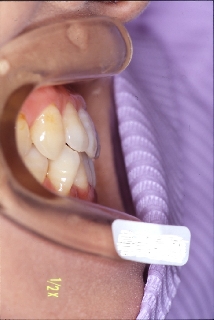

当院にて前歯部の被蓋の改善を行った。

右側面 右側面 右側面